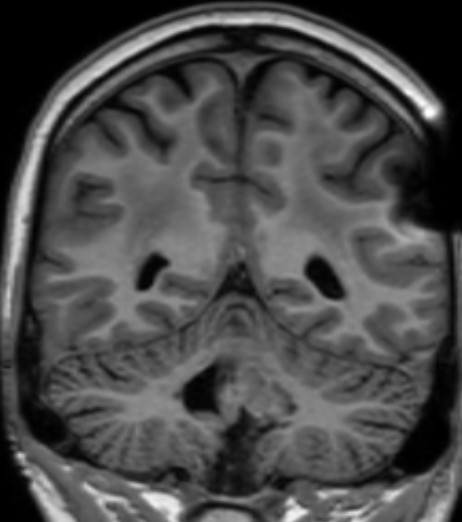

MRT Kopf – was sieht man?

Eine Kopf MRT liefert Ärzte und Radiologen detaillierte Bilder. Zu sehen sind das Gehirn, Schädelknochen, Blutgefäße und anderer umgebende Gewebe im Kopfbereich.

- Tumore und Zysten: Die MRT Kopf kann sowohl gutartige als auch bösartige Tumore im Gehirn erkennen. Sie kann auch bei der Identifizierung von Zysten und anderen strukturellen Anomalien helfen.

- Schlaganfälle und Blutungen: Auf den MRT-Bildern vom Kopf sind frische Schlaganfälle, Hirnblutungen und andere vaskuläre Probleme im Gehirn zu erkennen.

- Entzündungen und Infektionen: Entzündliche Zustände im Gehirn, wie Enzephalitis oder Abszesse, können durch die MRT Kopf Untersuchung identifiziert werden.

- Degenerative Erkrankungen: Die Kopf MRT kann bei der Diagnose degenerativer Erkrankungen wie Alzheimer oder Multipler Sklerose (Link) helfen, indem sie Veränderungen im Gehirngewebe zeigt.